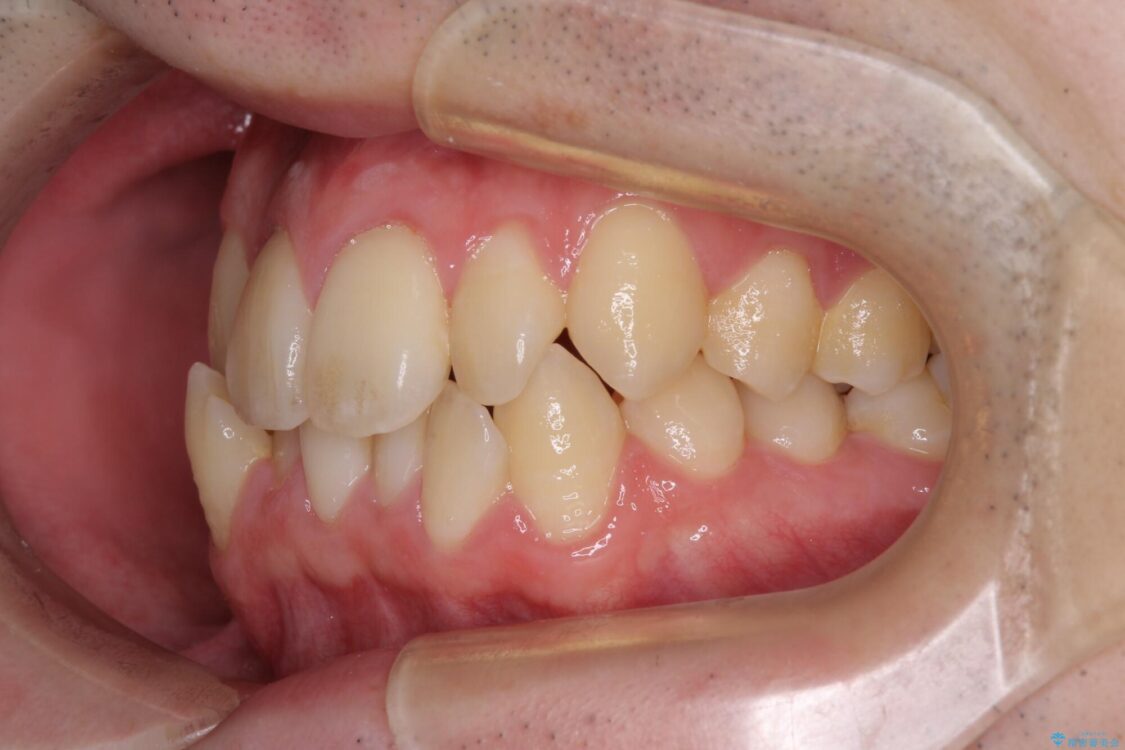

治療後

• 全顎的なクロスバイト 補助装置を用いてワイヤー矯正 治療後画像